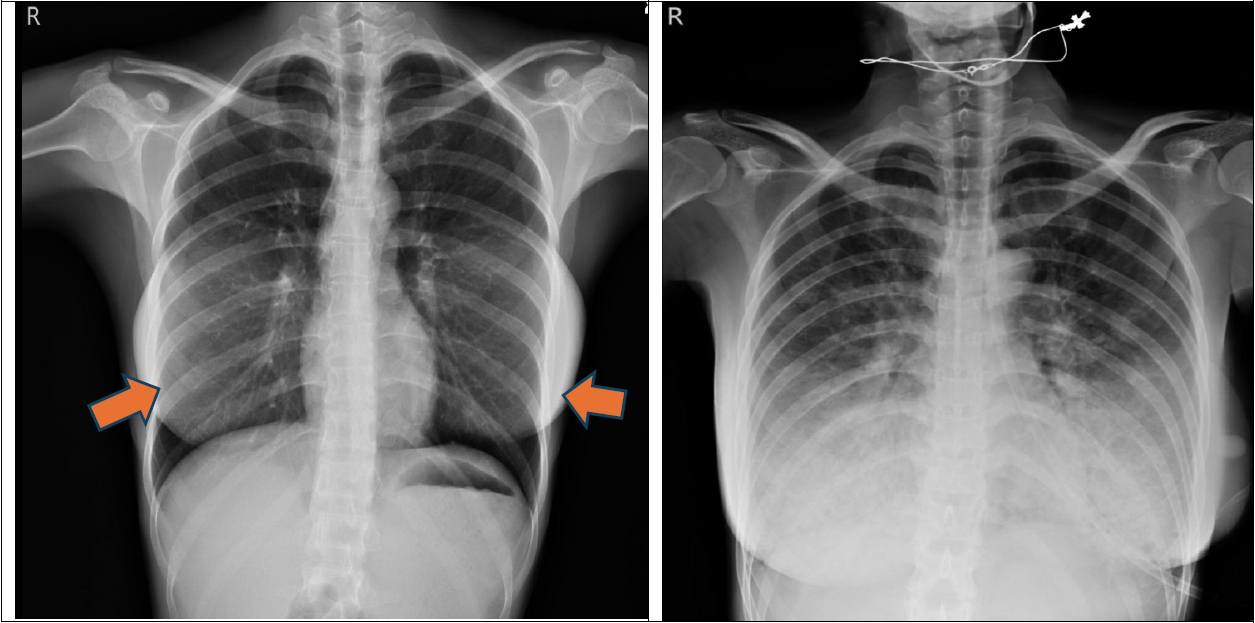

圖一、胸部X光片。左圖,之前就醫的X光片,肺部無明顯異常 ,雙側乳房手術植入假體(箭頭)。

右圖,此次就診的X光片,雙下肺部呈現明顯浸潤,雙側肋膜角度(CP angle)仍清楚可見銳角。

病人繼而轉住加護病房,給予氣管內插管,  支氣管肺泡灌洗後檢測的呼吸道病原體多標的核酸檢測無異常 ,心導管的檢查心臟血管也沒有阻塞,自體免疫的抗體檢查也正常。由於心臟衰竭嚴重(EF 22.8%),合併心因性休克,所以輔助以主動脈內氣球幫浦(IABP)。在經驗性抗生素和類固醇治療兩周,逐漸改善,拔除氣管內管並順利出院。 最後出院的X光如圖下:恢復正常的胸部X光片。